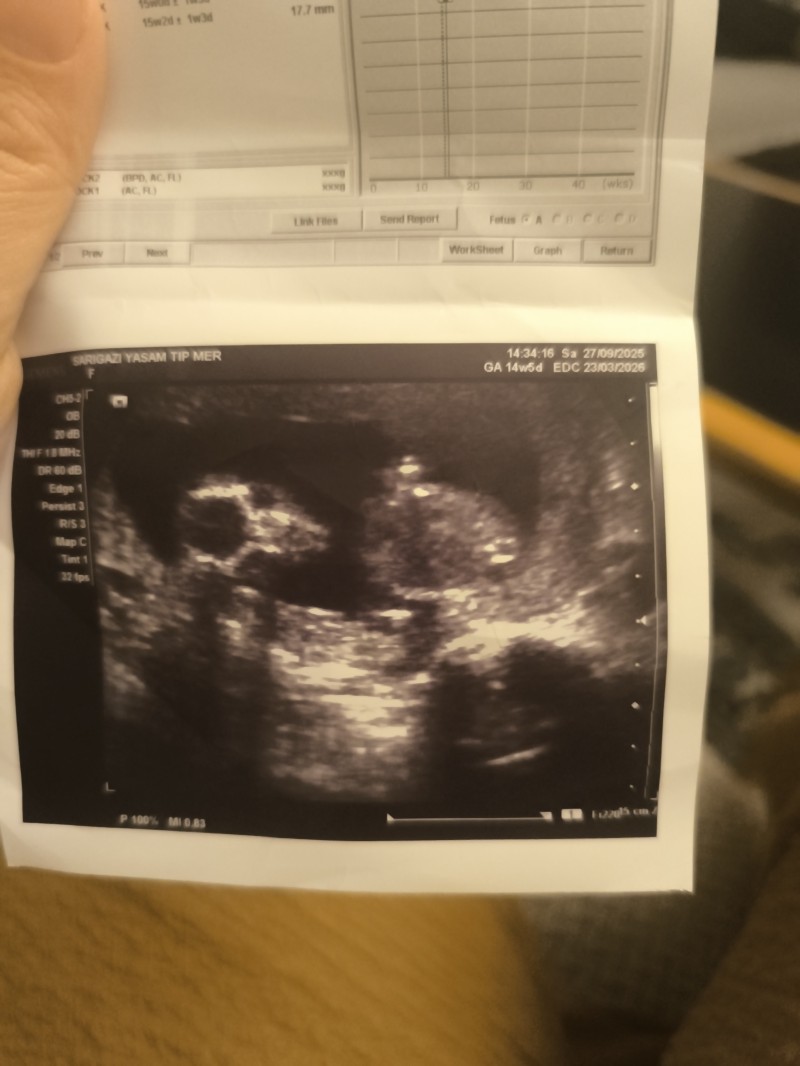

Cinsiyet tahmini yapar mısınız ne diyorsunuz kizlar

image

Bebek tam belli olmuyor ki olsada tahmin edemem zaten 😅

Belli canım yzu dönük burda oyuzden böyle çıkmış :D

İlk defa bir ultrasona tahmin yapamadım🤭

Yüzü dönük Muş burda :D kizlar